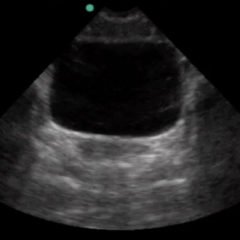

FAST Exam: Normal Morrison’s Pouch

FAST Exam - Normal Morrison's Pouch

radiology, normal, renal, Morrison’s pouch, trauma, liver, ultrasound, video, FAST exam